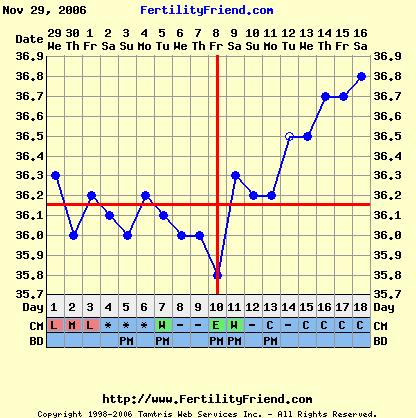

Éva, ez aztán a szép görbe! Igaz, én kicsi meglepődtem, hogy a 10. napon volt a pé-ed, de mivel nem esik vissza, tényleg akkor lehetett. Akkor viszont nemsokára tesztelhetsz!

Verzsike, szerintem ebből a görbéből még akármi lehet. A legjobb egy + volna a tesztek sávjában!

Ez a leesés akár beágyazódás is lehetett!!!

Addig is a semleges görbém.